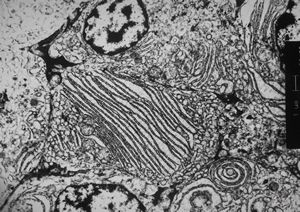

M,33y. | blood - hairy cell leukemia- ribosome-lamella complexin tricholeukocyte